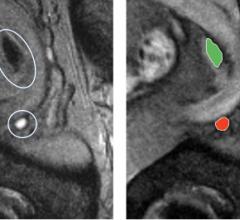

March 5, 2020 — Using a combination of magnetic resonance imaging (MRI) to target and sample suspicious prostate tissue ...